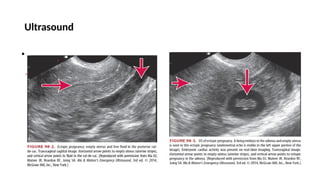

Ultrasound

• .

The Discriminatory Zone •The discriminatory zone is between 6,000 and 6,500 mIU/mL • A level above the discriminatory zone indicates an intrauterine pregnancy • A level below the discriminatory zone suggests an abnormal pregnancy, such as an ectopic pregnancy • Transvaginal ultrasounds are more sensitive than abdominal ultrasounds, so they can diagnose pregnancies earlier